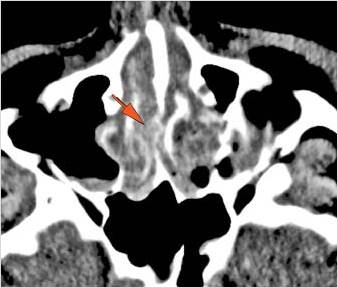

The circumferential extraconal and the intraconal orbital fat are edematous. [Yes/No]

There is evidence of a subperiosteal hematoma along the medial wall, roof or floor of the orbit. [Yes/No]

The orbital apex and the superior and inferior orbital fissures are abnormal. [Yes/No]

The extraocular muscles are swollen. [Yes/No]

Proptosis is present. [Yes/No]

The optic nerve has a stretched appearance. [Yes/No]

The posterior aspect of the globe is tented. [Yes/No]

There is evident general optic sheath swelling or swelling at the junction of the globe and sheath to suggest an optic sheath hematoma. [Yes/No]

There is evident subretinal, subchoroidal or intravitreous hemorrhage. [Yes/No]